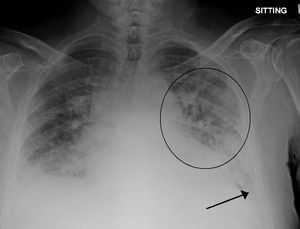

- Инструментальное. На ЭКГ выявляются признаки пароксизмальных нарушений, острого коронарного синдрома, ишемии миокарда (коронарная т-волна, подъем сегмента ST). Рентгенография свидетельствует о снижении пневматизации полей легких по типу снежной бури, при альвеолярной разновидности просматривается затемнение в виде бабочки. На УЗИ сердца определяются признаки гипокинезии левого желудочка.

- Рентгенография органов грудной клетки. Выявляет расширение границ сердца и корней легких. При альвеолярном отеке легких в центральных отделах легких выявляется однородное симметричное затемнение в форме бабочки; реже - очаговые изменения. Возможно наличие плеврального выпота умеренного или большого объема.

Рентгенография - позволяет подтвердить наличие отека легких и гипертрофию миокарда: расширение сердечной тени, линии Керли (Б), симптом «крыльев бабочки», однако нужно учитывать, что в 20% случаев на рентгенограмме отек легких не находит своего отражения;